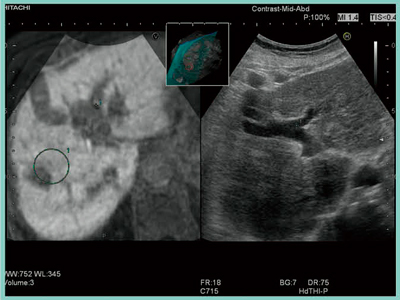

日立アロカメディカル社では今回,RVSで軸同期も可能となった。軸同期は,まず仮想画像の軸方向(X,Y,Z)を患者の体軸に合わせて登録する。そして,仮想画像とリアルタイムUSの同じ部位をポイントした直後に,三次元的に同期させることが可能となる。これを“シンプル・アジャスト”と呼ぶ(図1)。

図1 シンプル・アジャスト

仮想画像とリアルタイムUSの同じ部位をポイントした瞬間の画像。

この直後に同期する。